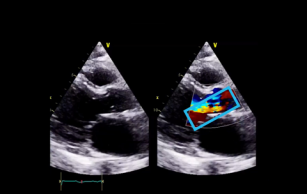

Detecting aortic regurgitation with echo 19th May 2017 - Helen Rimington, PhD After watching this video, you will be able to recognize hemodynamically significant aortic regurgitation using ...